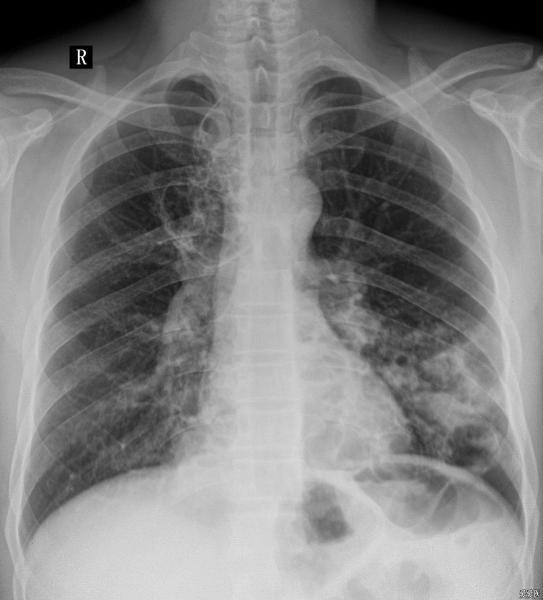

胸部正位DR片——双肺多发透亮影

患者男,40岁,咳嗽、咳痰伴发热、纳差一周。

右上肺及左下肺多发囊状阴影,左下肺伴发片状影,考虑多囊肺伴感染。鉴别:1.支气管扩张,多发生下肺,有咳血史。2.肺结核空洞,厚壁、上肺多见,伴咳血、低热的结核症状3.肺脓肿,单发、厚壁伴液平多见。4.肺癌空洞,单发、壁结节、厚壁等。